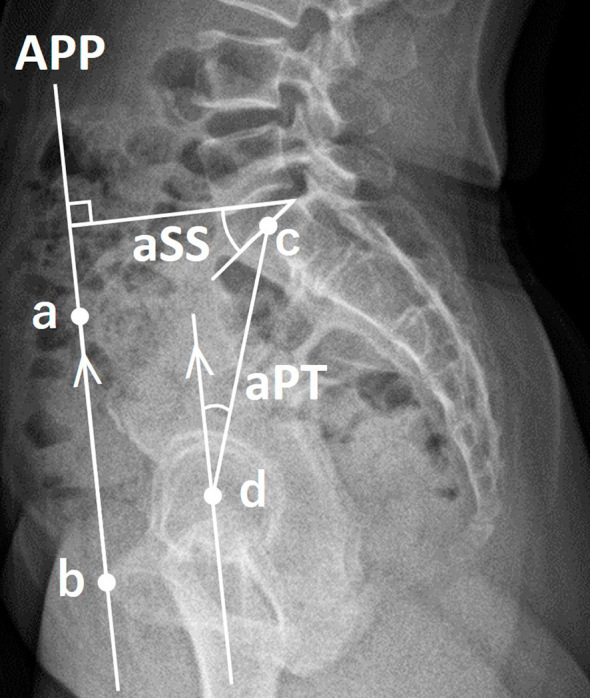

Methods: We analyzed biplanar, slot-scanning, full-body stereo radiography of 140 healthy Japanese volunteers (mean age, 39.5 years; 59.3% women). The APP was defined by bilateral anterior superior iliac spines and anterior surface of the pubis symphysis. Anatomical sacral slope (aSS) and anatomical pelvic tilt (aPT) were calculated as angles of the SS and PT regarding the APP.

Results: The APP was tilted anteriorly in the sagittal plane by an average of 0.7°. Anatomical pelvic parameters significantly correlated with standing sagittal parameters, except for cervical lordosis and T4-12 thoracic kyphosis (TK) (p<0.05). L4-S1 lumbar lordosis (LL) significantly correlated with aPT and aSS, but not with pelvic incidence (PI). In addition, T1-12 TK significantly correlated with aSS. Multiple linear regression analysis for lumbar alignment produced the following equations: L1-S1 LL (°)=0.588×aSS+30.522, L4-S1 LL (°)=0.165×aSS-0.248×aPT+32.825, lordosis distribution index (%)=-0.662×PI+102.8.